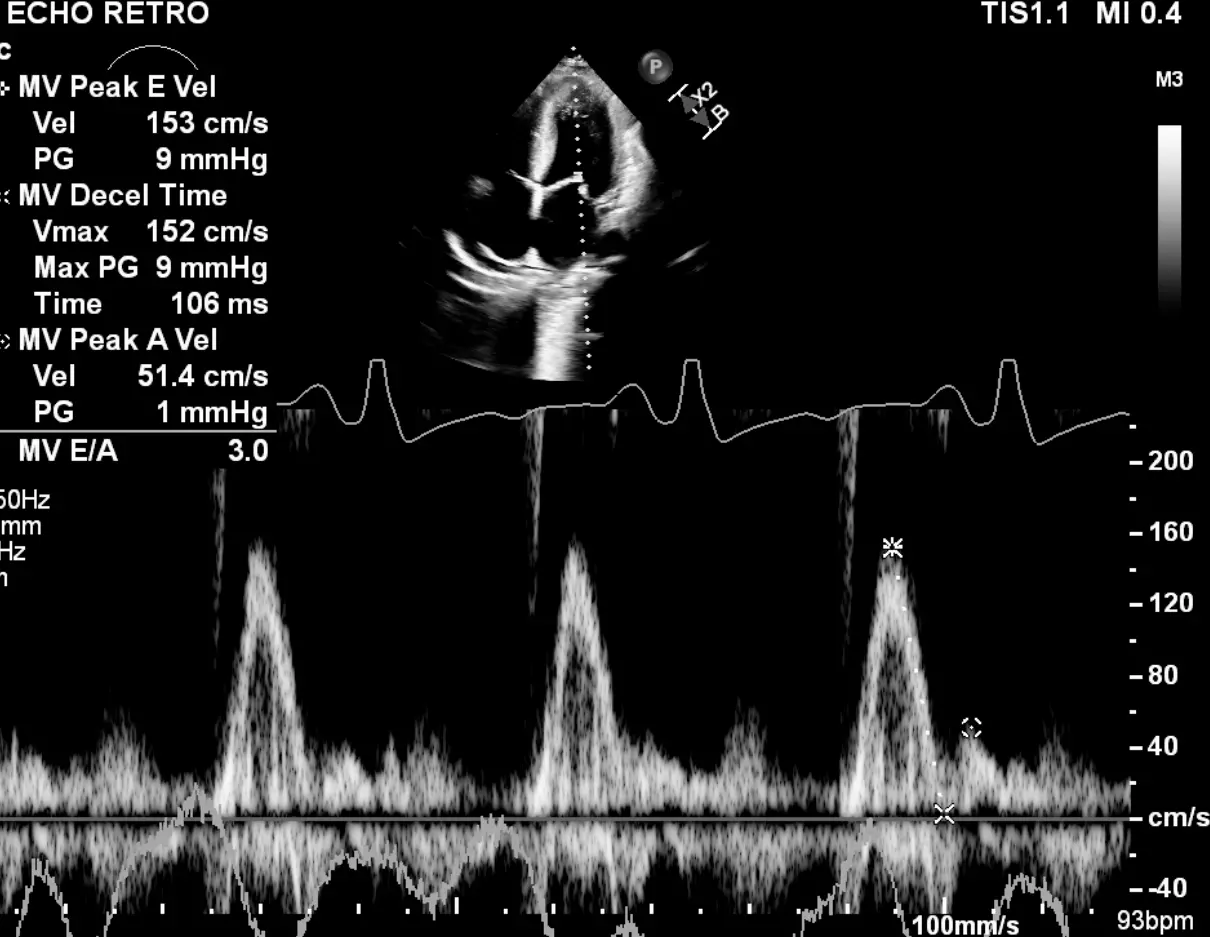

Mitral inflow pattern in a ~30 yo patient with severe LVH who initially presented with HTN emergency.

If you just base it off the patient having medial e’ >6, lateral e’ >7, or average >6.5, then you may conclude that she has normal diastolic function. However, I’d argue that this would be incorrect. The patient is a ~30 yo with severe LVH. Bearing in mind her young age, you should expect her e’ velocities to be much higher if she truly had normal diastology. With her very high E/A ratio, she has Grade 3 DD.